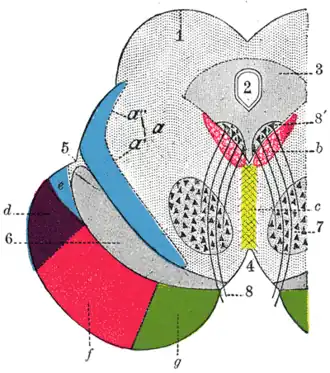

Coronal section through mid-brain.

The frontopontine fibers or frontopontine tract are corticopontine fibers projecting from the cortex of the frontal lobe to the pons. In the internal capsule, the fibers descend predominately in the anterior limb (but some also in the posterior limb), passing inferior to the thalamus to reach the mesencephalon (midbrain) where they descend in the medial portion of base of the cerebral peduncles. In the pons, the fibers flare out between the pontine nuclei.[1]: 460